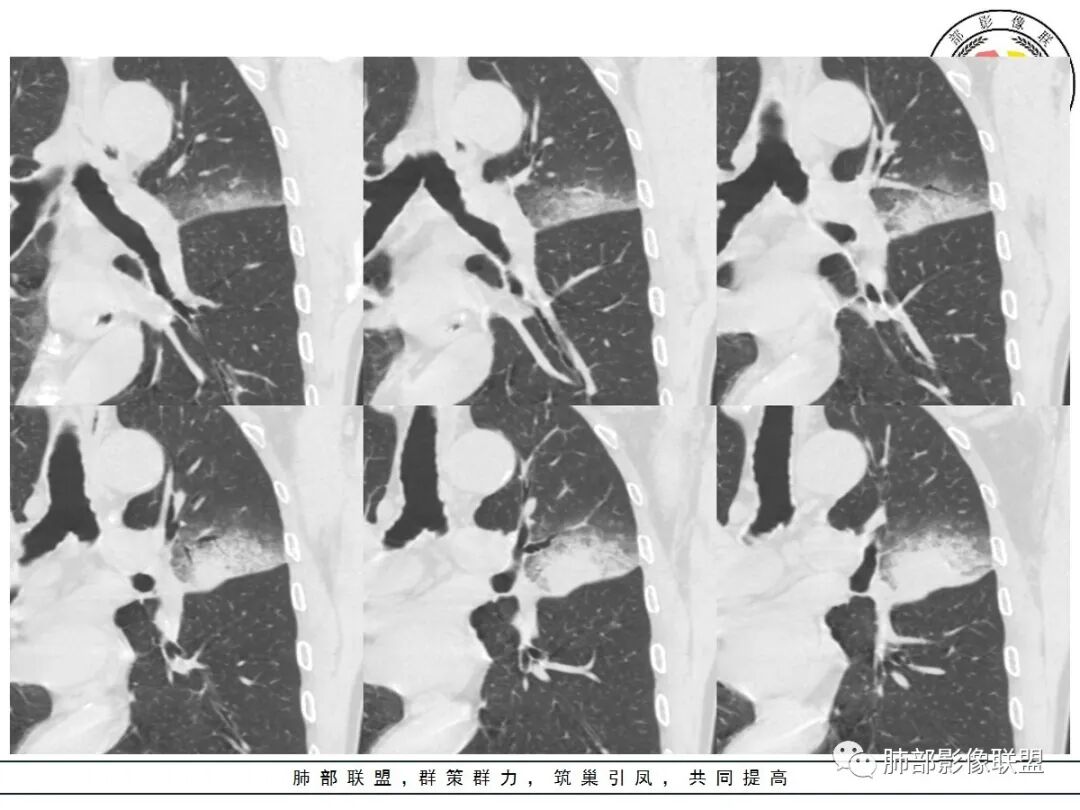

1、团片状,实行密度区外观整体圆顿,位于上叶尖后段与下舌段区间。局部膨隆,但未见分叶,肿瘤多见。

2、偏心空腔病灶,气腔略呈新月形,壁不规则,腔内结节相对密实,明显强化且不均,支持新生物而非曲菌球等。炎性空洞多有强化环。

3、病变强化较明显,其内隐约显示多发小斑片状无强化灶,可疑边界不清小灶坏死区。病灶内血管影浅淡、模糊不规则。

4、支气管改变:上舌段支气管远段延入部分稍示僵硬。尖后段见分支支气管阻塞,恶性多见。

5、周围磨玻璃,3个月后逐渐转为密实,应符合当初附壁生长为主,且逐渐向实体成分转换。

6、病变长轴平行且受限于胸膜,外围大内带小,符合外朝内发展病变。“腔内结节状明显强化”加之支气管改变有力支持新生物诊断。如此大范围边界不清的磨玻璃影让人浮想联翩。如此大范围病灶,肺门纵隔未见肿大淋巴结也让人意外。